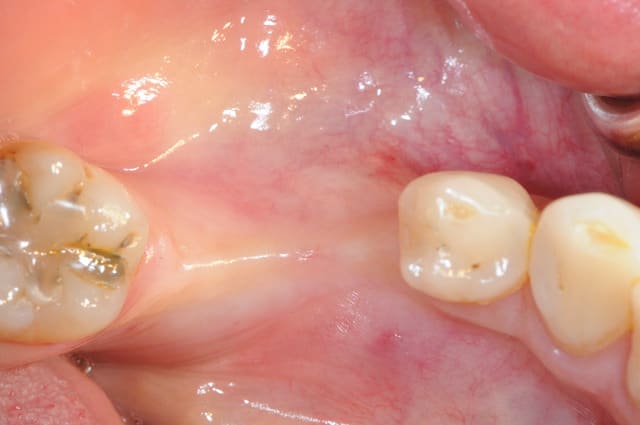

1-2-3 situation de départ

4 après ouverture